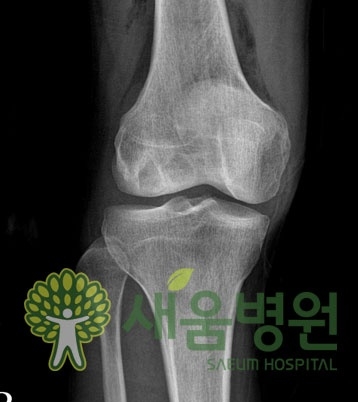

반월상 연골판은 무릎 관절 내에서 충격을 흡수하는 역할을 하는 초승달 모양의 연골 조각이다. 간혹 이 초승달 모양의 반월상 연골판이 반달 혹은 보름달 모양을 띄는 경우가 있는데, 이것을 ‘원판성 연골’이라고 한다. 사실상 원판성 연골은 반월상 연골판의 기형적 형태라 할 수 있으나 생활에 크게 불편을 느끼거나 통증을 일으키지 않아 자신도 모르고 지나치는 경우가 많다.

하지만 구조적 특성상 원판성 연골판은 반월상 연골판에 비해 충격 흡수에 약하고, 탄력성도 떨어져 손상이 일어나기 쉽다. 무릎에서 자주 소리가 나고, 무릎을 펴기 힘들며 계단을 오르내리기 힘들어지는 증상이 흔히 나타나는데, 이런 경우에는 MRI 검사 결과와 전문의 진료에 따라 수술적 치료가 필요할 수 있다.

연골판에 대한 진단은 환자의 증상과 의사의 상담만으로도 어느 정도 추측이 가능하지만 좀 더 명확한 진단을 위해서는 자기공명영상(MRI) 검사를 하는 것이 좋다. 또 관절내시경으로도 검사가 가능한데, 이는 CT나 MRI로 파악하기 어려운 질환의 상태도 정확하게 진단은 물론 동시에 수술도 시행할 수 있다는 장점이 있다.